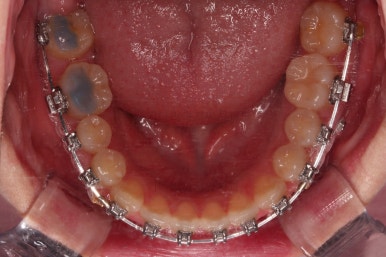

폭이 맞아지고 치아 배열을 조금 시행하니 송곳니 부분에서의 반대교합이 금새 개선된 것을 알 수 있으실거에요.

이렇게 측방으로의 반대교합만 개선이 되어도 턱관절에서의 불편감은 많이 줄어들게 됩니다.

윗니는 가지런하게 하는 동안 아랫니는 중앙선을 개선하기 위해 미니스크류를 이용해 뒤로, 뒤로 계속 당겨주게 됩니다.

힘 조절도 적절히 해가면서 아래 치열을 뒤로뒤로 옆으로 옆으로 밀어줍니다.